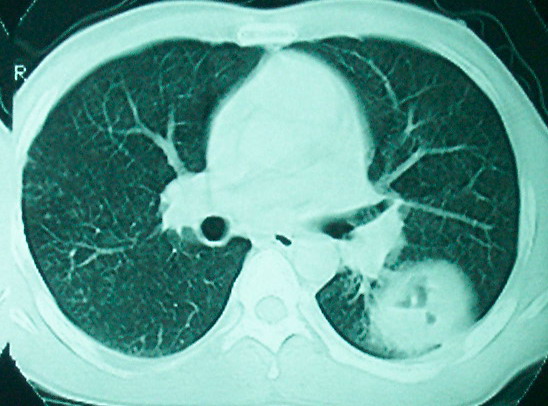

m      37y      发热   咳脓痰月余      ct肺脓肿但住院抗炎治疗后双肺内结节不知该如何解释

治疗后见左肺下野病灶较前缩小但双肺内结节影似无变化请较各位老师该如何下结论    治疗前wbc14.5 治疗后wbc 11.0

我看是不是可以两元化来解释,左肺下叶还是肺脓疡,而其余病灶考虑肺癌伴肺内转移,我看右肺上叶尖段病灶可见明显毛刺改变为原发病灶.

1、左下肺鳞癌伴两肺及纵隔淋巴结转移;

2、两上肺支扩伴慢性炎症。

左下肺病灶除了明显的厚壁空洞 气液平外,明显见壁结节,另两肺多发小结节,综合考虑:左下肺周围性肺癌伴肺内转移.

如果你仔细的同层面对比,你会发现所有的病灶均有比较明显的吸收、缩小。病变的形态,特别是脓肿的形态、壁的厚薄、内壁均有很大的变化,均在往好的方面发展。与临床症状、血像均符合,治疗效果比较显著,就是肺脓肿并双肺的化脓性炎症灶。